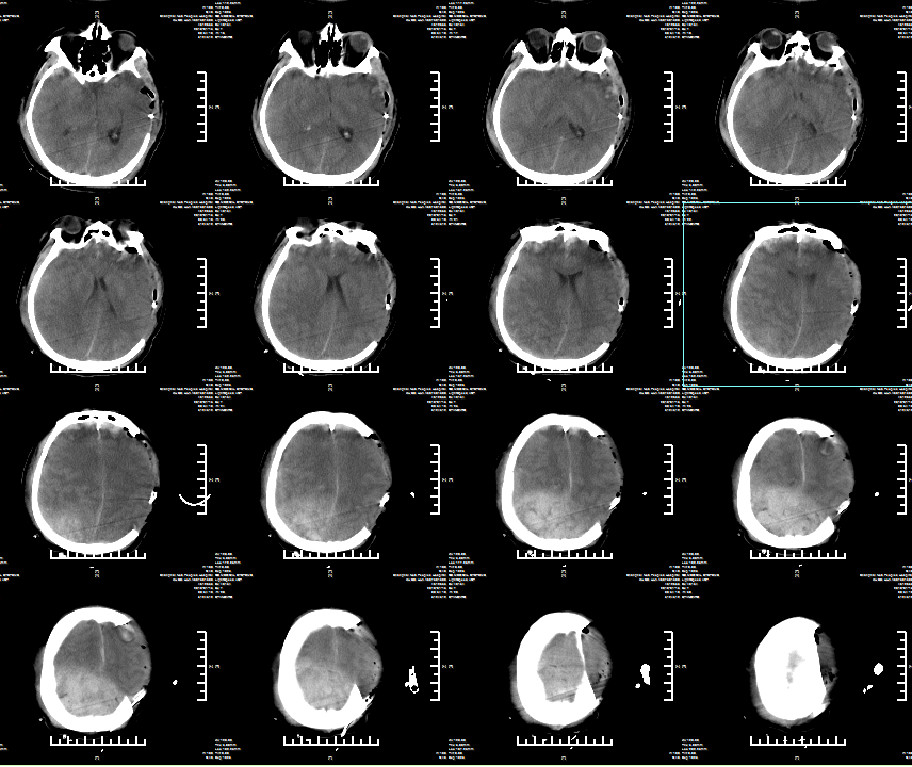

术后常规复查头颅CT(2019年1月15日9点54分):右顶硬膜外出血急诊行右顶硬膜外血肿清除术。

二次术后常规复查头颅CT(2019年1月15日16点04分)

患者心率105次/分,血压90/62mmHg,氧饱和度100%,ICP13-25mmHg。口插管呼吸机支持,SIMV,TV480ml,RR12bpm,PS10cmH₂O,PEEP5cmH₂O,FiO₂45%。2019年1月15日ICU血气检验报告:PH7.21↓,二氧化碳分压59.0mmHg ↑,氧分压127.0mmHg ↑,乳酸5.90mmol/L ↑,碳酸氢根浓度23.6,全血碱剩余-5.0mmol/L ↓。2019.1.15日血常规:Hb84g/L,红细胞比积24.3%。2019年1月15日急诊化验检验报告:凝血酶原时间15.1秒 ↑,国际标准化比率1.33 ↑,部分凝血活酶时间43.1秒 ↑,纤维蛋白原2.472g/L ,凝血酶时间14.9秒 ,抗凝血酶Ⅲ活性59.7% ↓,D二聚体4.68mg/L FEU ↑,纤维蛋白(原)降解产物15.3mg/L ↑。考虑患者失血性休克,创伤性凝血功能障碍,酸中毒;予镇痛、镇静、调整呼吸机过度通气,纠正酸中毒,输冰冻血浆400ml,冷沉淀10个单位,凝血酶原复合物,去甲肾上腺素微泵维持血压及脑灌注压,常规脑保护治疗。患者口插管呼吸机支持,SIMV,呼吸频率20次/分,PC10cmH₂O,PS10cmH₂O,PEEP5cmH₂O,吸入氧浓度40%,潮气量在480-500ml。T 36.6度,HR 101次/分,血压128/67mmHg(去甲肾上腺素0.3ug/kg/min),氧饱和度100%。ICP在20-30mmHg之间波动。查体:镇静中,两侧瞳孔等大等圆,对光反射迟钝。两肺呼吸音粗,未及明显干湿啰音。腹软,无明显肌紧张,无压痛、反跳痛。血气:PH7.41 ,二氧化碳分压41.0mmHg ,氧分压117.0mmHg ↑,乳酸3.00mmol/L ↑,白蛋白(干式)21g/L ↓,肌钙蛋白-I0.286 ↑,CKMB6.4ug/L ↑,肌红蛋白251.3ug/L ↑。血红蛋白53g/L ↓,血小板65X10^9/L ↓。给予加强镇痛、镇静;去甲肾上腺素维持血压;输悬浮红细胞、血小板及血浆,白蛋白,注射用美罗培南+万古霉素抗感染治疗。